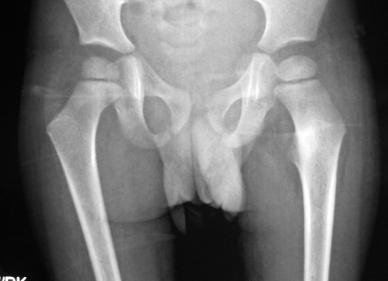

8Yr old presented with painful left sided limp & pain over left hip and thigh since 6 months. It was a boring kind of pain moderate to severe in intensity and getting relieved by Ibuprofen (NSAIDs).

X-ray showed increased bone density at the region of lesser trochanter

CT showed the typical nidus in the center of a transluscent lesion in the same region of increased density – OSTEOID OSTEOMA (Benign bony tumor)

Required open surgery where the lesion was well excised and the patient recovered well. Biopsy confirmed the diagnosis. No symptoms since 3 years of surgery.